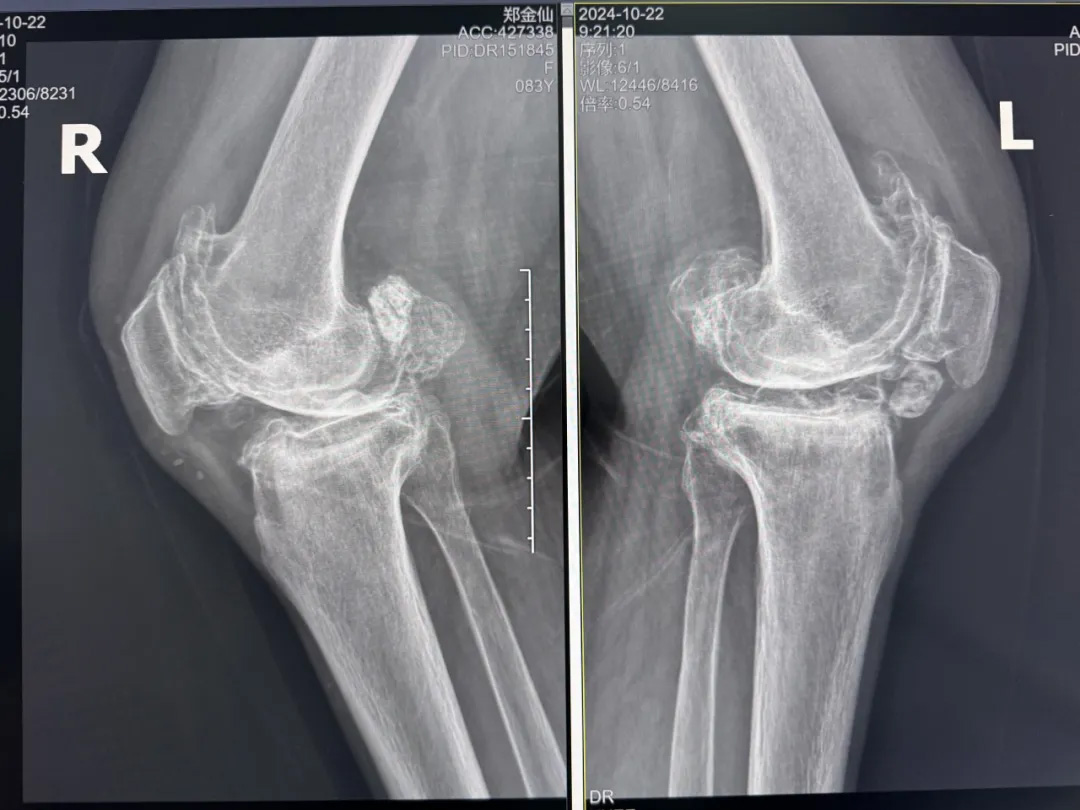

年輕時(shí)愛(ài)到處走走的鄭阿婆,晚年卻被雙膝劇痛困在輪椅上長(zhǎng)達(dá)二十年。經(jīng)羅副院長(zhǎng)診斷,她的膝關(guān)節(jié)軟骨幾乎磨光,關(guān)節(jié)嚴(yán)重畸形,呈"羅圈腿",走幾步便疼痛鉆心,連如廁都需家人抱扶。“我這輩子啊,估計(jì)再也站不起來(lái)了。”是阿婆最常說(shuō)的話。